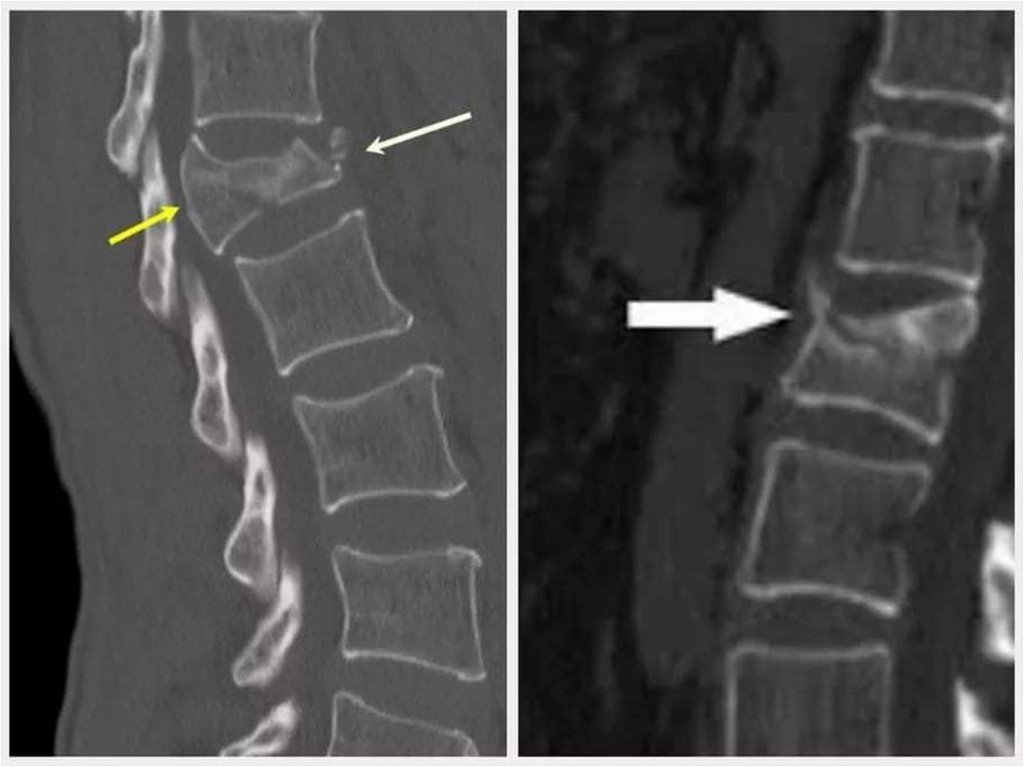

• Позвоночник:

1. Аномалии и пороки развития позвоночника и

спинного мозга;

2. Травмы позвоночника и спинного мозга;

3. Опухоли позвоночника и спинного мозга;

4. Дегенеративно-дистрофические изменения;

5. Воспалительные заболевания позвоночника;

6. Измерение минеральной костной плотности

при системном остеопорозе.